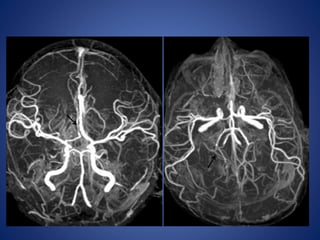

• Stenosis/occlusion of the distal ICA

• moyamoya vessels with signal voids in the basal ganglia

• ischemia

• infarction

• atrophy, and ventriculomegaly.

• Small abnormal net-like vessels proliferate giving "puff of smoke"

appearance.

• Contrast-enhanced T1WI - marked leptomeningeal enhancement

along the cortical sulci (ivy sign).

often show contrast stagnating in slow-flowing collateral

vessels both in the brain parenchymal and over its surface.

MR imaging

5 yrs male child with history of left sided focal seizures with secondary generalization